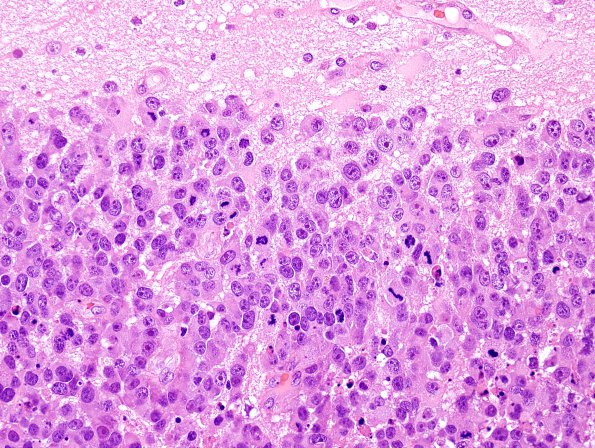

Washington University Experience | NEOPLASMS (METASTASES) | Microscopic | 52B2 Metastasis, large cell neuroendocrine CA (Case 52) H&E 12.jpg

Sections of the "right frontal tumor" show sheets and nests of neoplastic cells with abundant cytoplasm with round, hyperchromatic nuclei containing prominent nucleoli, and numerous mitoses